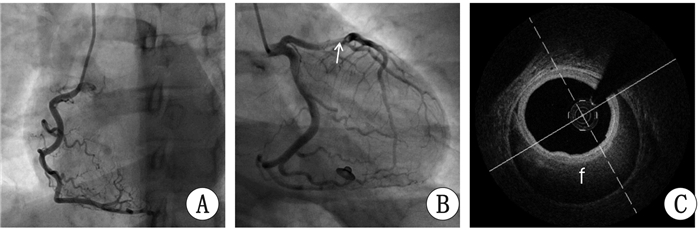

病例3 患者,女,因“停经34周,胸痛6 h”于2016年11月14日入院。2016年11月13日22时突发胸骨后持续性胀痛,当地医院心电图:Ⅰ、aVL导联ST段抬高0.05~0.1 mV,Ⅱ、Ⅲ、aVF、V1~V5导联ST段压低0.05~0.15 mV。考虑急性冠脉综合征,遂转本院。入院查体:BP125/65 mmHg,神清,两肺呼吸音清,心率90次/min,律齐,腹隆,胎动正常,胎心140次/min。CK-MB 202 U/L,TNI>50.000 pg/mL,NT-proBNP 73 pg/mL。心电图:I、aVL导联异常Q波,V1~V2导联T波负正双向。心超:左心室前壁及部分侧壁心肌运动明显减弱,LVEF58%。诊断:孕34周单活胎,急性心肌梗死。予以单硝酸异山梨酯、地尔硫卓等治疗后胸痛缓解,与家属商议后当日行冠脉造影:左主干未见明显狭窄;左前降支近段及中段40%狭窄,第一对角支起始部70%狭窄(图 4A、B)。行OCT检查提示:左前降支近段及中段壁内血肿,累及对角支开口,前降支血管内膜完整(图 4C)。经多学科会诊后于2016年11月14日成功行剖宫产术。剖宫产术后逐步加用拜阿司匹林、氯吡格雷、美托洛尔等治疗,未再发胸痛。

| 图 4 病例3冠脉造影及OCT。白色箭头示左前降支自发性夹层,f示假腔 |